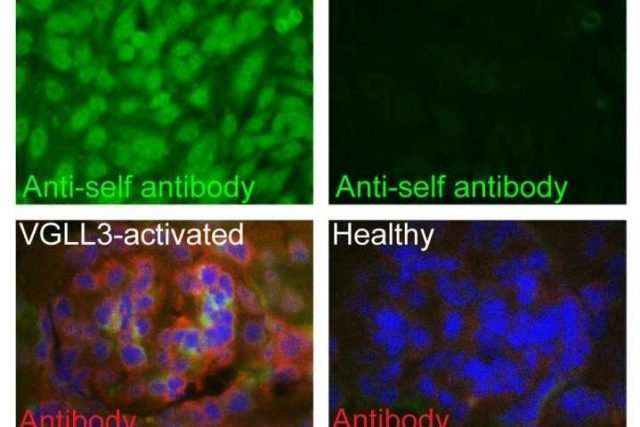

Mengapa Lebih Banyak Wanita Terkena Penyakit Autoimun Dibanding Pria?

Salah satu misteri terbesar dari dunia medis, dan juga mempengaruhi hidup jutaan orang ialah: mengapa gangguan sistem imun lebih sering menyerang wanita dibandingkan pria? Penyakit autoimun, seperti lupus telah menyerang wanita sembilan kali lebih besar dibandingkan pria. Jawaban dari pertanyaan diatas ternyata ada pada salah satu bagian dari tubuh kita, kulit. Penelitian terbaru telah menemukan bukti tentang peran penting dari molekul...